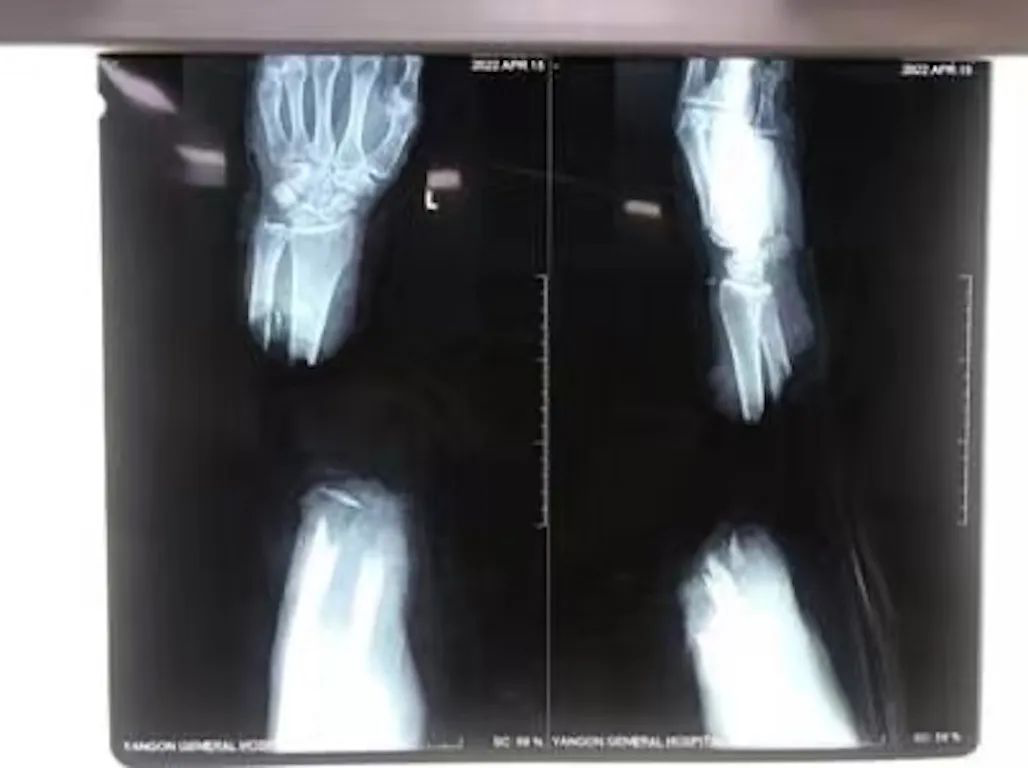

【缅甸金凤凰讯】据缅甸卫生部网站报道,4月14日,仰光综合大医院为一位患者成功进行了断手连接手术。

该患者居住在仰光省九文台镇区,从事捕鱼业。4月14日下午3:00,他因意外被刀将左手腕上方砍断。当日下午5:55,患者前往医院就医。医生、护士和卫生工作人员为患者进行紧急治疗,及时与手外科专科医生联系,并进行紧急手术。

由仰光综合大医院手外科博士生漂貌貌率领的手术组,当天晚上7:50开始进行断手连接手术,次日清晨1:30手术结束。手术结束后,患者的血管慢慢恢复循环,4月25日开始在关节炎科门诊部进行恢复锻炼,4月29日获准出院。